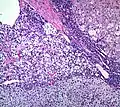

Histopathology

The microscopic histopathology analysis of the tissue samples obtained from the adrenal cortex of individuals presenting with adenoma-associated symptoms such as primary aldestronism (PA) indicates that adenoma cells are relatively larger with different cytoplasm, and increased variation in nuclear size. This indication is based on comparison between the healthy (normal) and affected (adenoma-associated) adrenal cortex tissue samples.

- Adrenocortical adenoma with focal high grade nuclear atypia

- Adrenocortical adenoma with focal necrosis

Adrenocortical adenomas are most commonly distinguished from adrenocortical carcinomas (their malignant counterparts) by the Weiss system,[10] as follows:[11]